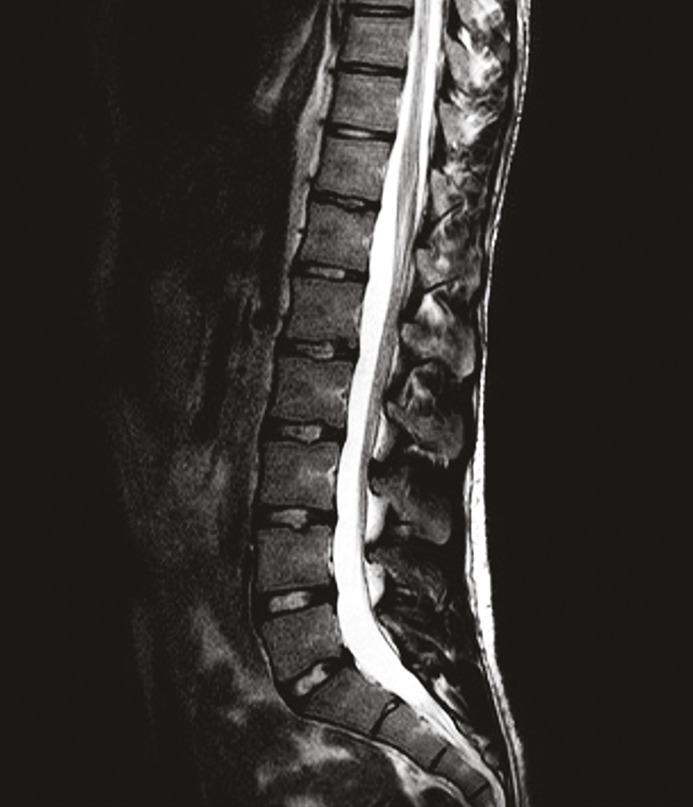

Le patient est hospitalisé pour surveillance et une imagerie par résonance magnétique (IRM) est réalisée (fig. 2). Celle-ci met en évidence une légère déformation et un refoulement antérieur du cordon médullaire à hauteur de la vertèbre T6 avec discret hypersignal intramédullaire focal en regard, sans prise de contraste associée. Aucune autre anomalie n’est visualisée au niveau du cordon médullaire. Aucune masse intramédullaire ou intracanalaire n’est objectivée.

Une imagerie par résonance magnétique (IRM) est réalisée dans un délai raisonnable, pour exclure des anomalies osseuses, affections neurologiques, hématomes post-traumatiques ou autres signes de lésion du nerf pudendal.4